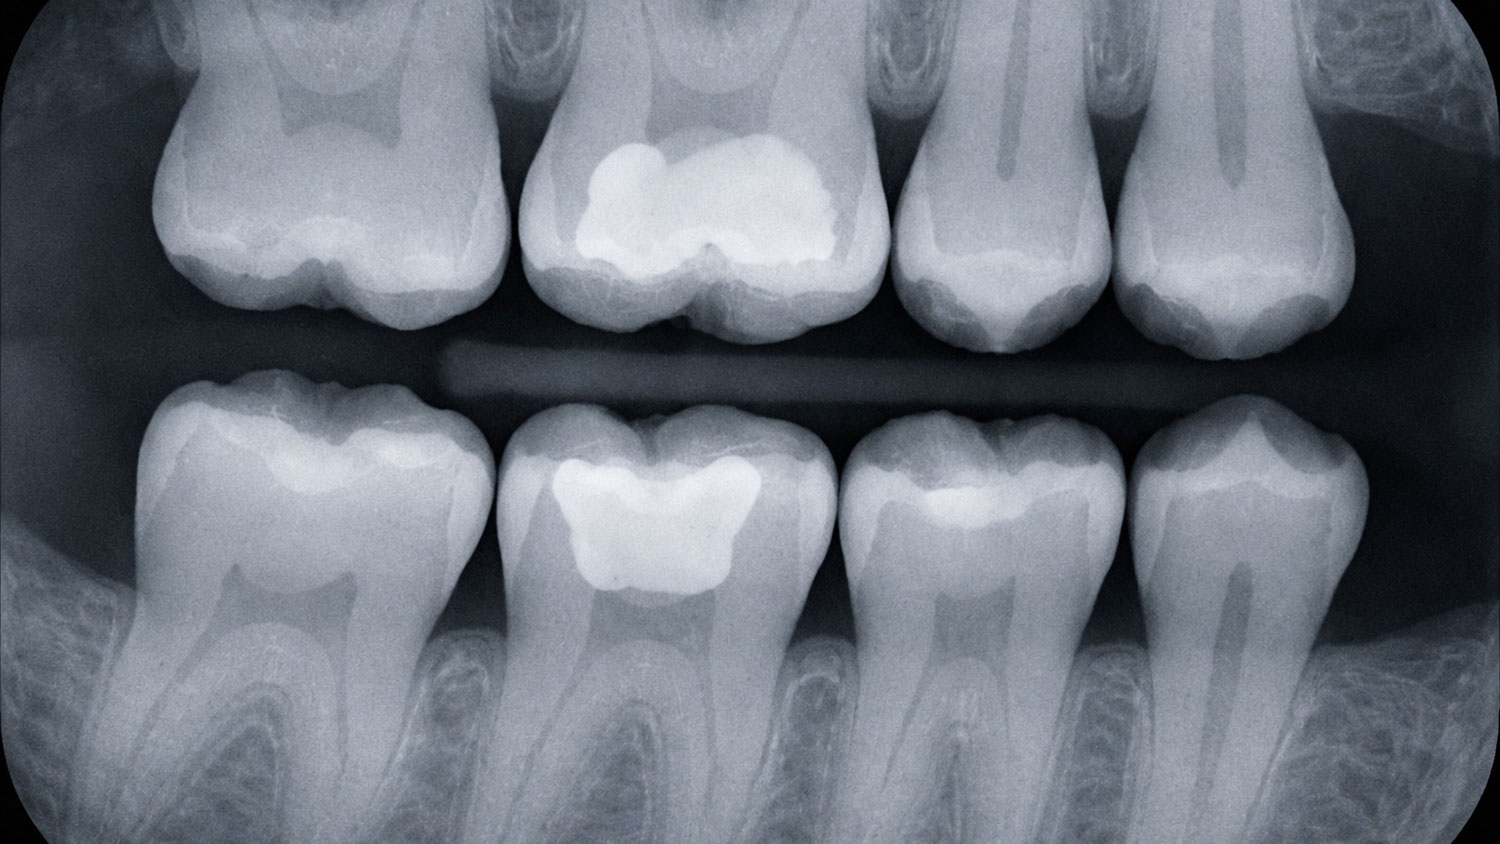

バイトウィング

むし歯の進行を最小限に抑えるためには、見逃さないことが重要です。歯と歯の間や修復物の下など、視診では確認が難しい部位まで把握することができます。早期発見・早期対応により、歯を長く守ることにつながります。

年に一度の撮影をおすすめしております。